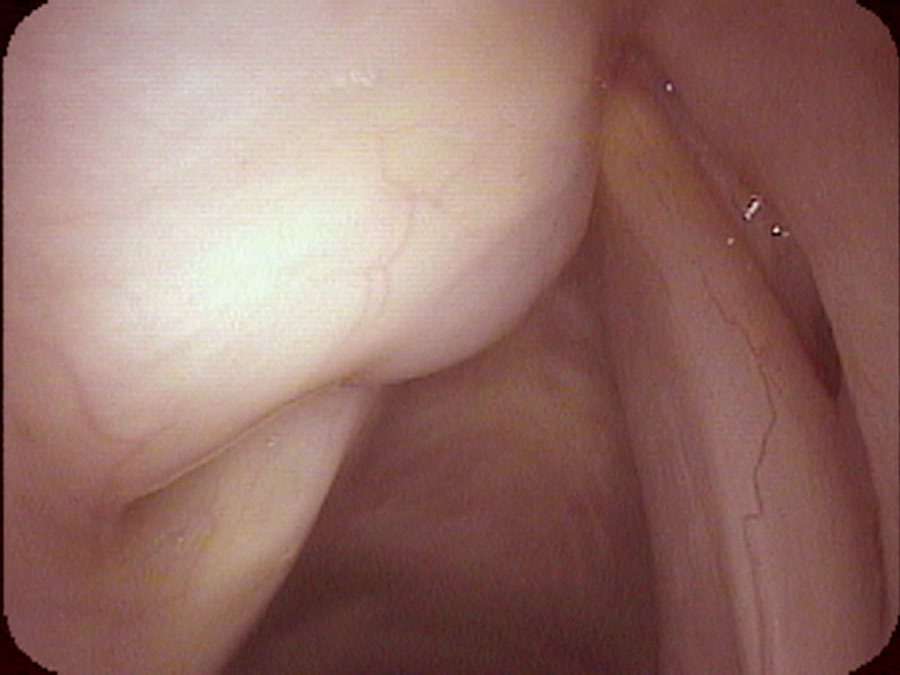

I ultimately numb her vocal cords so that I can place my endoscope underneath the smooth, round, swollen left false vocal cord. The left false vocal cord is dilated and obscures the left true vocal cord. There is a fluid-filled cyst enlarging the left false vocal cord. The left vocal cord is also not moving and in the view during inspiration, the left vocal cord remains positioned near the midline. Even on a close-up view it is difficult to see the left true vocal cord. I actually have to lift the swollen false vocal cord up with the endoscope to see the true vocal cord.

I anesthetize her vocal cords and put the endoscope almost on the vocal cords and watch them vibrate when she makes sound. The left-sided saccule has enlarged to the point that it pushes down on the true vocal cords. This pressure on the vocal cords dampens their vibrations. It then requires more air or effort to start and to keep the vocal cords vibrating. Her saccular cyst is actually causing her vocal effort and her weak voice — by rubbing on both vocal cords when she tries to make a sound. Even though she has an obvious left-sided vocal cord movement impairment, it is only a striking visible abnormality and not actually the cause of her weak voice.